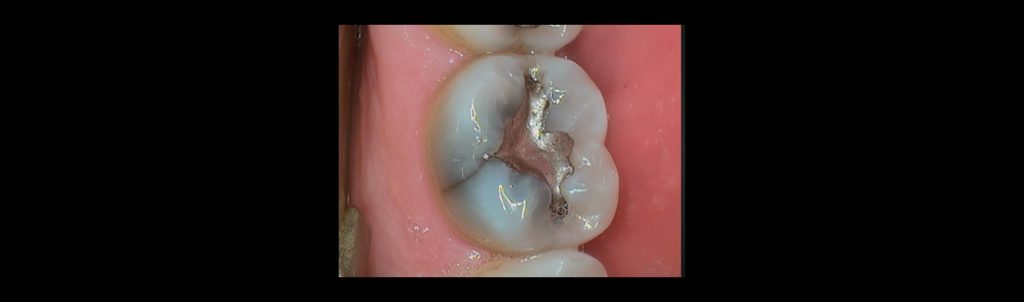

Fractured cusp

The most common fractured cusp is the distolingual cusp of lower molars, particularly second molars. This pattern is linked to Class III lever mechanics and occlusal forces near the temporomandibular joint (TMJ). Upper molars are more resistant due to their anatomical structure and the support they receive from the transverse ridge.

Cuspal fractures may be lateral or vertical, which are the worst case. Factors contributing to cusp fracture include parafunction, cumulative masticatory load, sudden trauma, and previous restorations. Restored teeth are 30 times more likely to fracture than unrestored teeth. Pulp involvement varies.